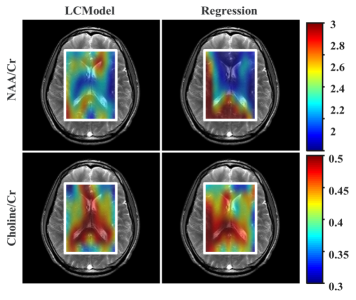

Synthetic (Spectra) - Real (Images). We test our synthetic spectra training model on the 2D MRSI data and the results are shown in the boxplot in Fig. 5 along with the resulting concentration distribution from both the regression approach and the non-linear model fit. As our synthetic model is trained for only NAA and Cho ratios, we show the errors for these two only. Median estimate error for NAA/Cr is 0.24 using regression. For Cho/Cr, the estimation error is 0.34. The corresponding concentration values estimated from the LCModel serves as our ground-truth.

Real (Spectra) - Real (Images). We perform a blind test with 96 2D MRSI spectra against the training model generated using the 287 SVS spectra and the results are shown in Table. 1. Median estimate error for NAA/Cr is 0.1, for Cho/Cr is 0.18, for mI/Cr is 0.217 and for Glx/Cr is 0.13. Although we expect the errors to be higher in the blind test due to difference in the acquisition protocols of the training and testing dataset, the errors appear to be within a reasonable window. As expected, the estimated errors are highest for mI/Cr while Glx/Cr surprisingly has a lower error than Cho/Cr.